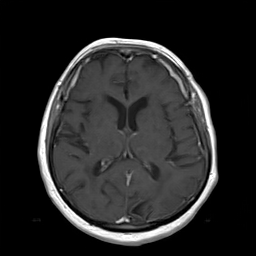

(a) Guide 𝑮𝑮\boldsymbol{G}

(b) Input 𝑰𝑰\boldsymbol{I}

(c) Guidance map 𝑴𝑴\boldsymbol{M}

(d) Prediction 𝑷𝑷\boldsymbol{P}

(e) Ground truth

(f) Guide 𝑮𝑮\boldsymbol{G}

(g) Input 𝑰𝑰\boldsymbol{I}

(h) Guidance map 𝑴𝑴\boldsymbol{M}

(i) Prediction 𝑷𝑷\boldsymbol{P}

(j) Ground truth

Figure 2: Inputs and outputs of the guided filtering pipeline based on the WDSR network. T1 & T2 MRI pairs (a)-(e) and CT & MRI projection images (f)-(j).